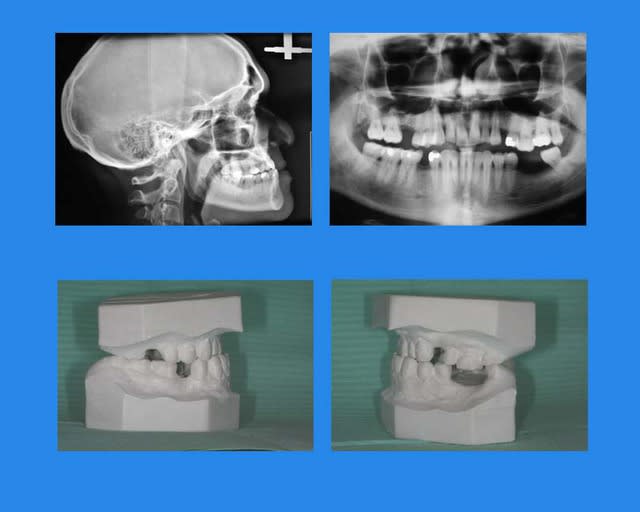

Cas terminé

rectification: voici son profil fin de TTT.,